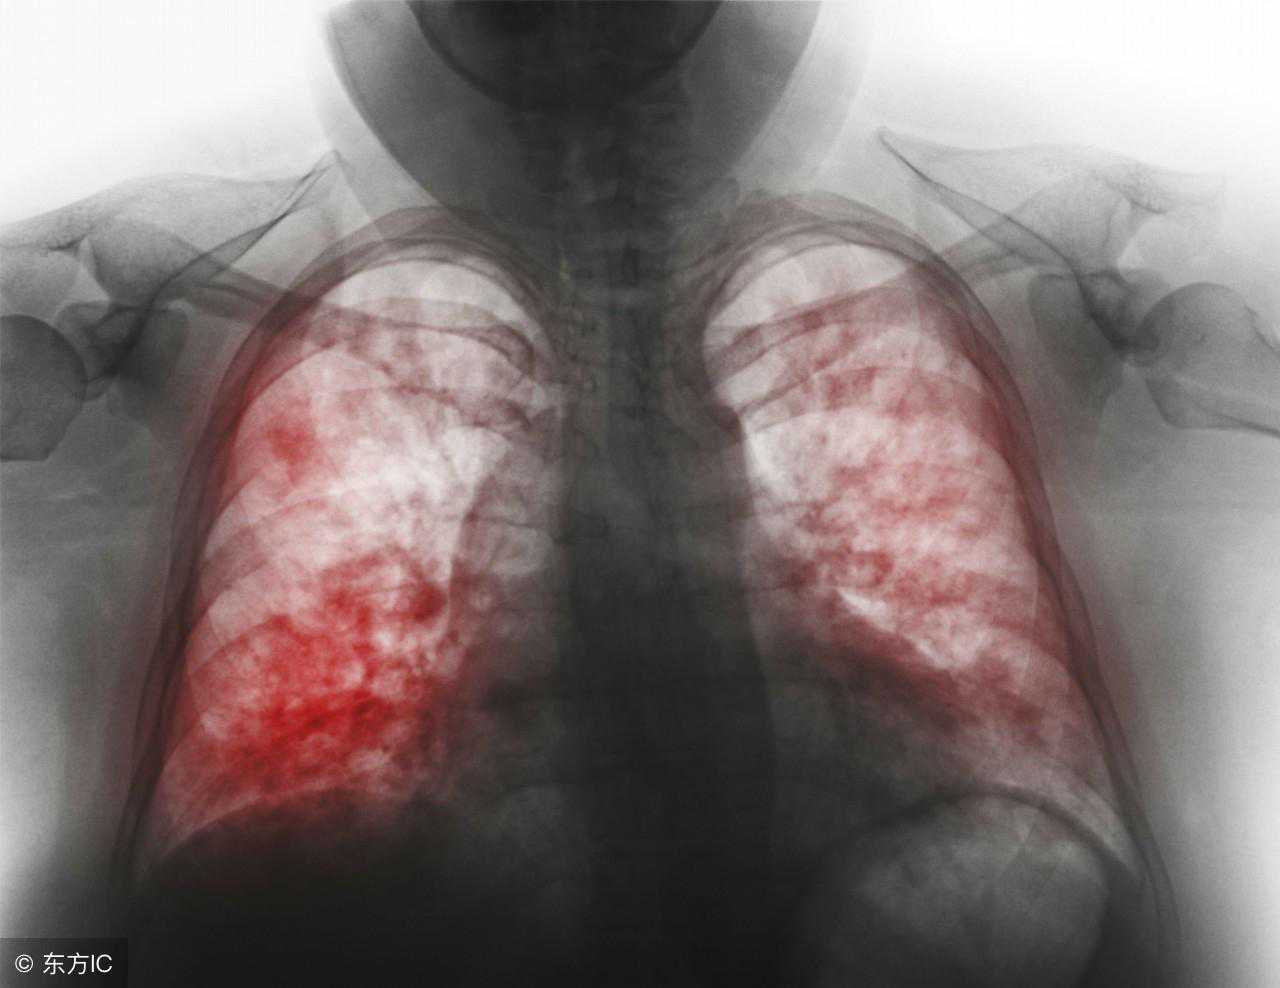

⑺X线胸片显示双侧或多肺叶浸润影,或入院48小时内肺部浸润影扩大≥50%;

2.影像学检查影像学检查是诊断肺炎的重要指标,也是判断重症肺炎的重要指标之一。肺炎的影像学表现:片状、斑片状浸润性阴影或间质性改变,伴或不伴胸腔积液。影像学出现多叶或双肺改变、或入院48h内病变扩大≥50%,提示为重症肺炎。由于表现具有多样性,特异性较差。但影像改变仍对相关病原菌具有一定的提示意义(见表1)。